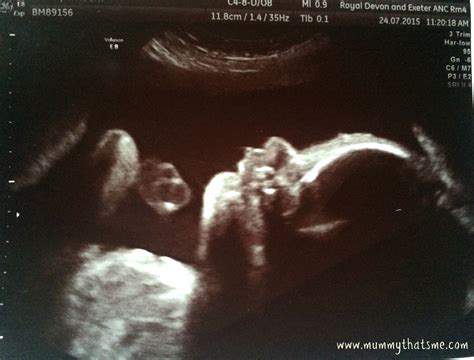

28 Weeks Sonography is a routine ultrasound scan conducted during the third trimester of pregnancy. This scan is often referred to as the "anomaly scan" or "mid-pregnancy scan" and is usually performed between 26 and 28 weeks of gestation. The primary goal of this ultrasound is to assess the baby's growth, development, and overall health. It also helps in identifying any potential complications that may require further monitoring or intervention.

During a 28 Weeks Sonography scan, the expectant mother will lie on an examination table with her abdomen exposed. A gel is applied to the abdomen to enhance the transmission of ultrasound waves. A transducer, a handheld device, is then moved over the abdomen to capture images of the baby. The procedure is painless and non-invasive, typically lasting between 20 to 30 minutes.

These measurements help in estimating the baby's weight and assessing overall growth. The technician will also check for any structural abnormalities in the baby's organs, such as the heart, brain, kidneys, and spine.

• Fetal Position: Determining the baby's position in the uterus can help in planning for delivery, especially if the baby is in a breech position.